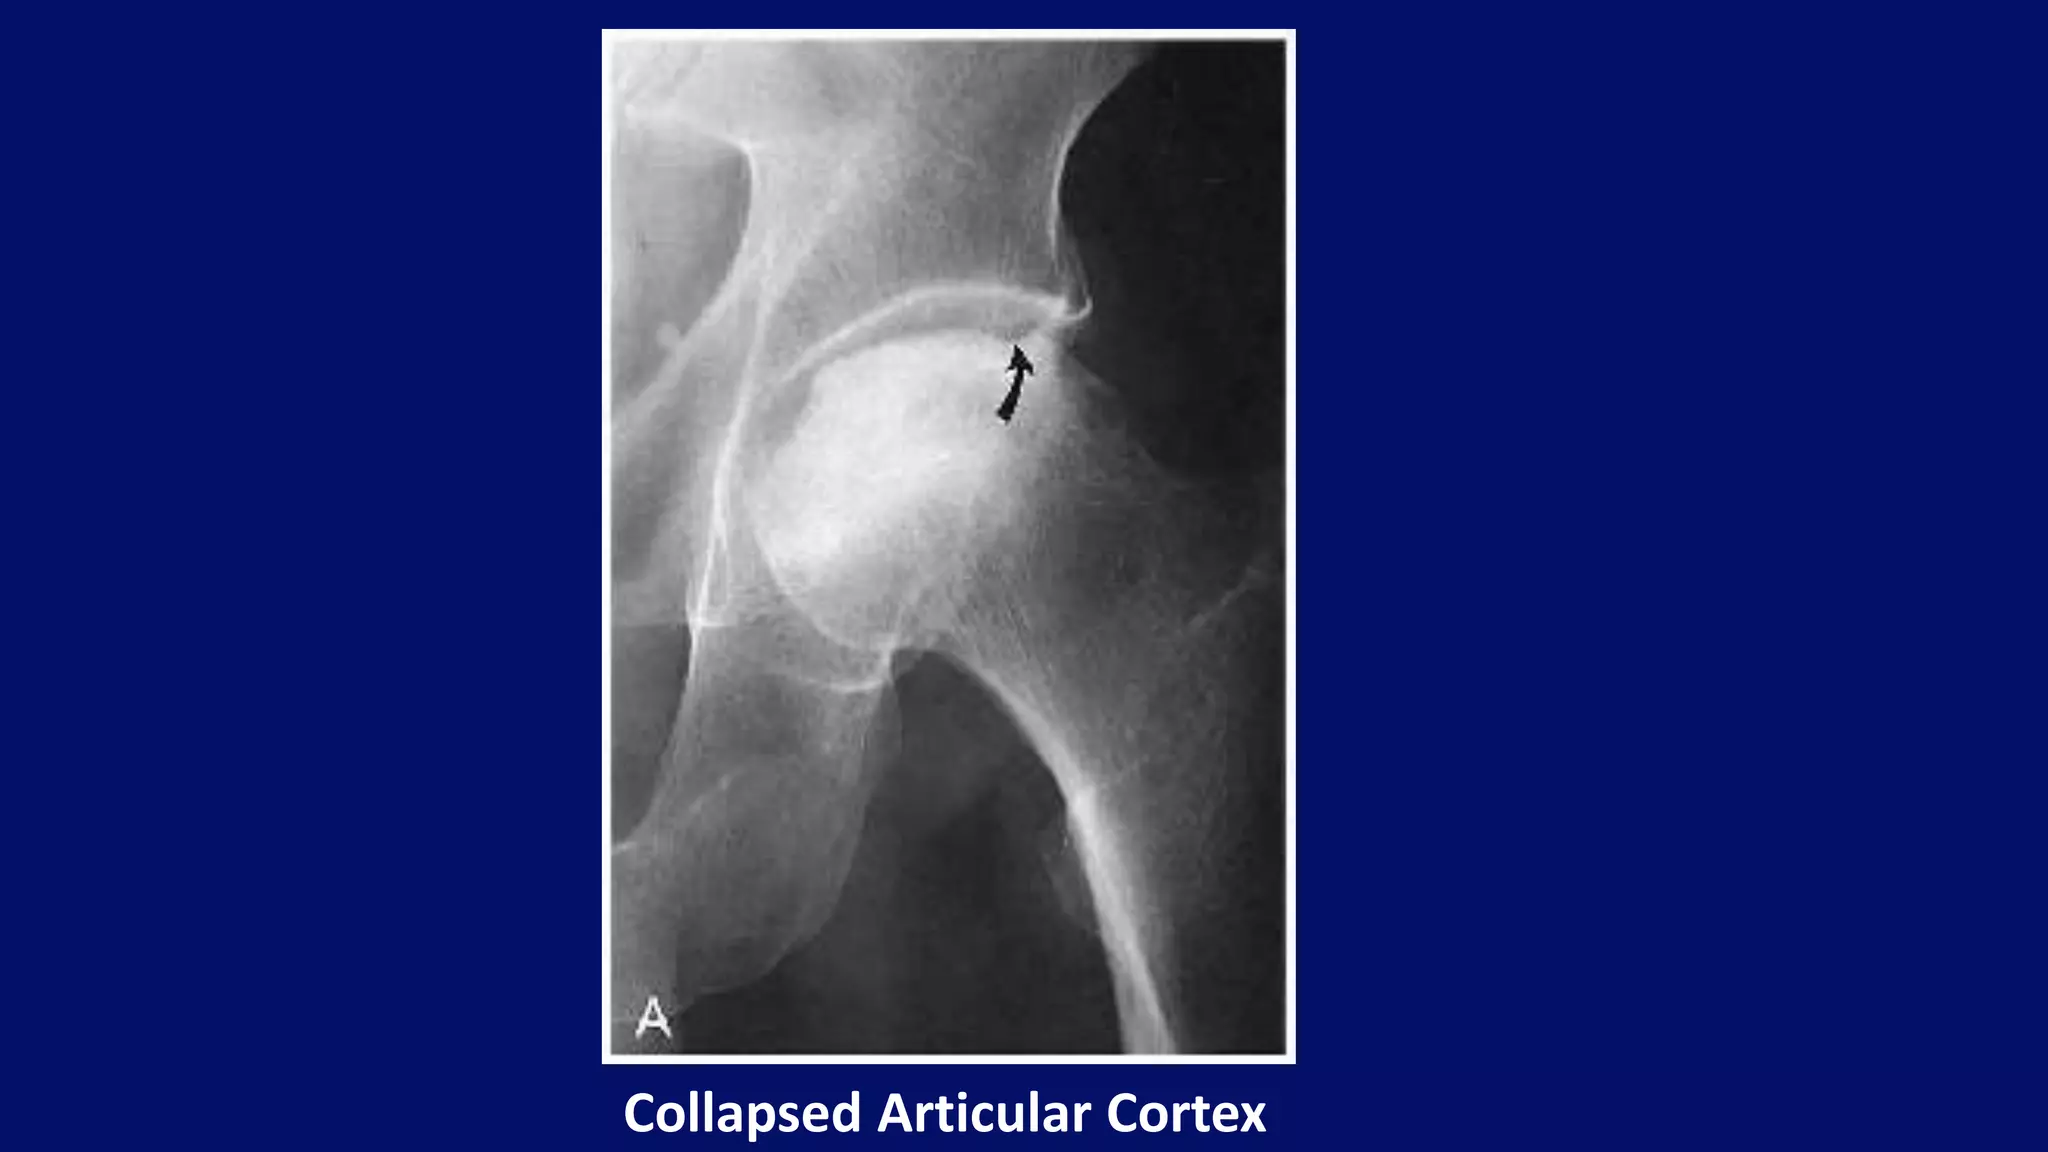

• Collapse of articular cortex

• Crescent sign (Subchondral fracture)

Radiographic features

Collapsed Articular Cortex

• #58 Collapsed Articular Cortex. Observe the sharp, angular deformity (arrow) in the weight-bearing cortex (step defect). Sclerosis of the femoral head is also evident.